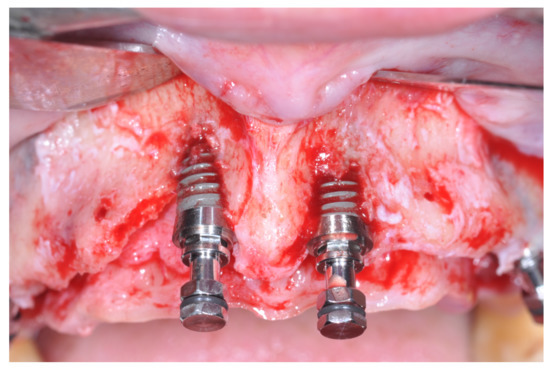

Figure 7. Placement of the dental implants.

Figure 8. Clinical view after prosthetic loading. One additional implant was inserted when abutments were placed on the four originally inserted implants.

At this point, a non-resorbable high-density PTFE barrier (Cytoplast TXT-200, Osteogenics Biomedical, Lubbock, TX, USA) was designed on the basis of the bone defect shape and was distally blocked on the bone by two titanium pins (Kalos, Nike, Orbetello, Italy). A mixture of 50% autogenous bone harvested from the mandibular ramus with the use of a scraper and 50% inorganic bovine bone (Bio-Oss, Geistlich, Wolhusen, Switzerland) was placed in the recipient site and the membrane was pulled and blocked on the bone with two mesial pins. With this particular, and innovative, non-resorbable membrane management, the graft was compressed and fixed on the recipient bed (Figure 9, Figure 10 and Figure 11). The occlusal portion of the graft was then covered with a layer of a collagen resorbable barrier (Bio-Gide, Geistlich) (Figure 12) and peri-osteal incisions were performed to make the flap passive.

Figure 9. Occlusal view after implant placement.